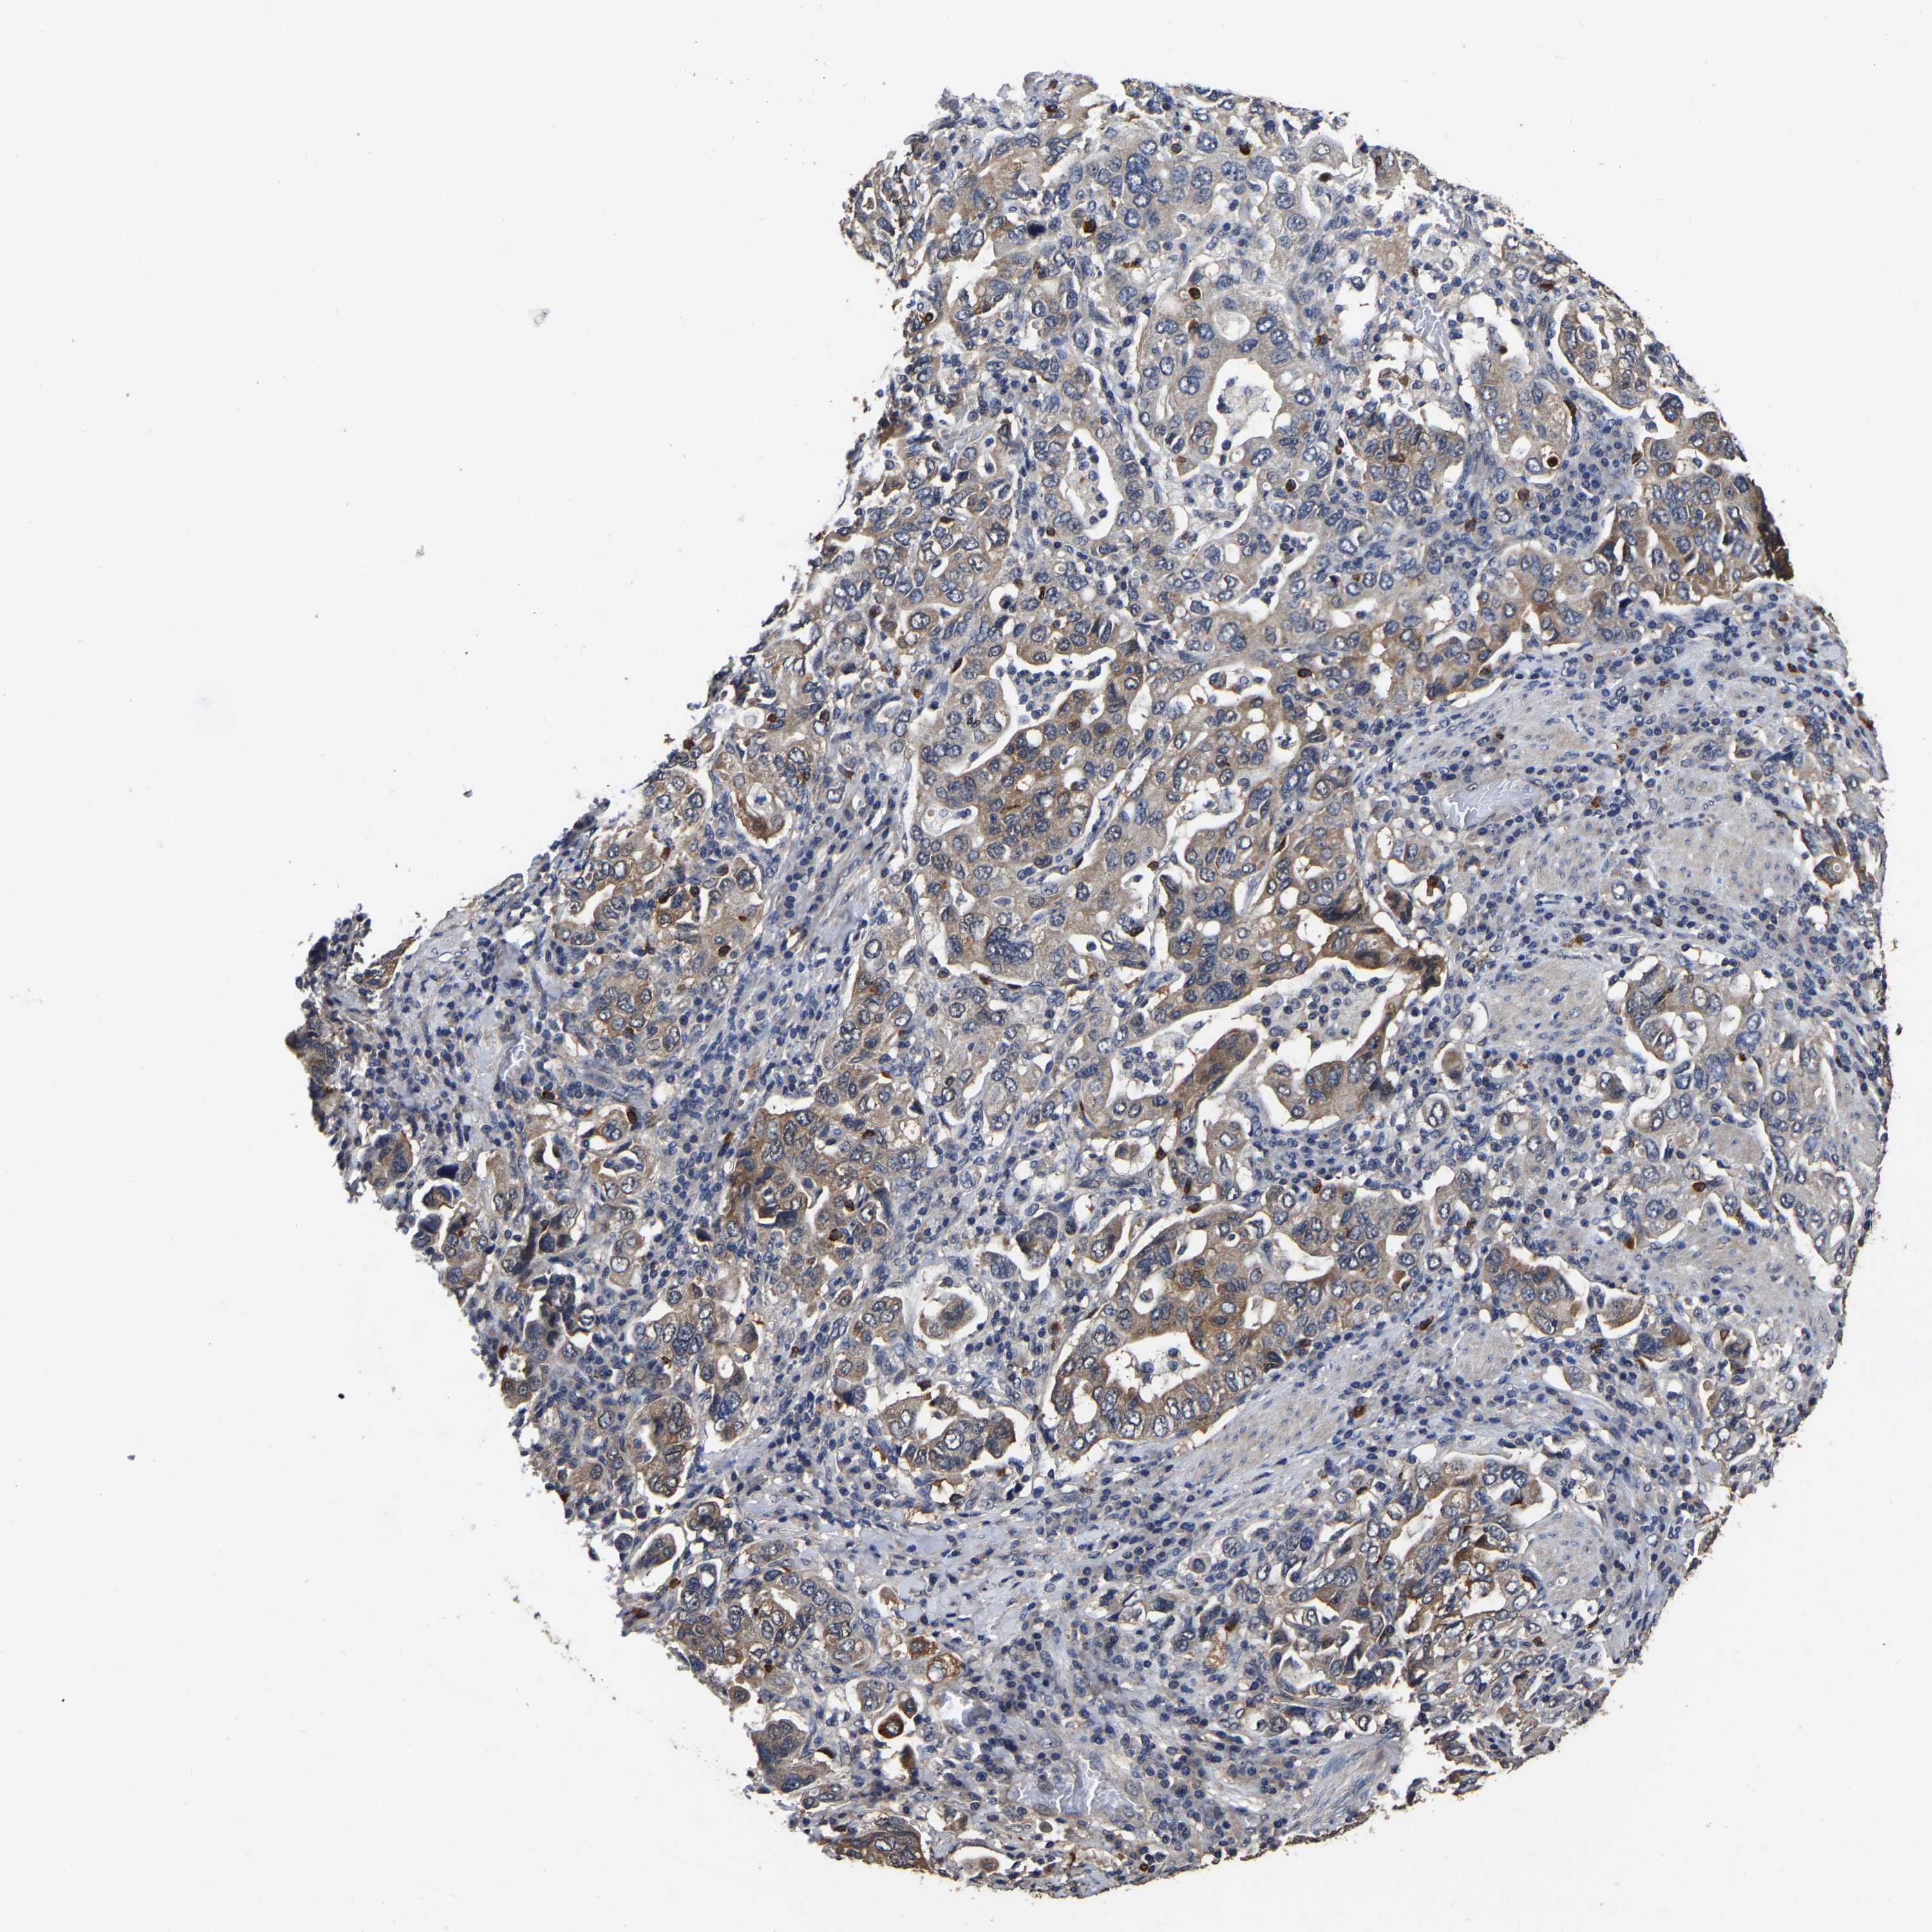

STOMACH CANCER - Protein expressioni

A mouse-over function shows sample information and annotation data. Click on an image to view it in a full screen mode. Samples can be filtered based on level of antibody staining by selecting one or several of the following categories: high, medium, low and not detected. The assay and annotation is described here.

Note that samples used for immunohistochemistry by the Human Protein Atlas do not correspond to samples in the TCGA dataset.

Antibody stainingi

Antibody staining in the annotated cell types in the current human tissue is reported as not detected, low, medium, or high, based on conventional immunohistochemistry profiling in selected tissues. This score is based on the combination of the staining intensity and fraction of stained cells.

Each image is clickable and will lead to virtual microscopy that enables deeper exploration of all samples and also displays staining intensity scores, fraction scores and subcellular localization as well as patient and tissue information for each sample.

Antibody HPA017894

Staining

High

Medium

Low

Not detected

Intensity

Strong

Moderate

Weak

Negative

Quantity

>75%

75%-25%

<25%

None

Location

Nuclear

Cytoplasmic/membranous

Cytoplasmic/membranous,nuclear

Adenocarcinoma, NOS